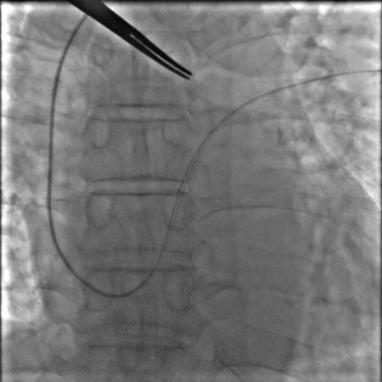

5月10日,心血管内科团队按照计划对老冯进行了手术。术中顺利穿刺左侧锁骨下静脉,经TIG导管、6F JR4导管顺利操作导丝通过卵圆孔进入左上肺静脉。虽然遇上加硬导丝送至左上肺静脉的困难,但团队迅速调整策略,送入260cm J形导丝,随后缓慢推送手工塑形后的180°8F输送鞘并顺利通过,送入并释放18*25mm卵圆孔未闭封堵器。通过透视及超声评估,封堵效果满意。

介入封堵过程:

a.导丝通过卵圆孔进入左上肺静脉;

b.输送鞘通过卵圆孔;